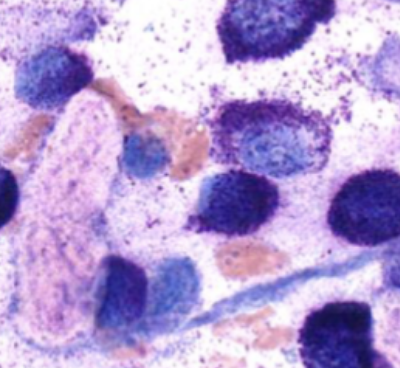

What is the first-line diagnostic test for MCT?

Fine-needle aspiration (FNA) cytology.

What stains are best to visualize mast cell granules?

Giemsa or toluidine blue.

Why might granules not stain with Diff-Quik?

Mast cell granules may appear unstained with this method.